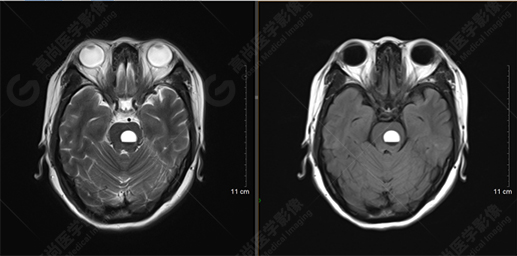

T2WI及FLAIR序列

影像表現(xiàn):橋腦見一類圓形異常信號(hào)影,直徑約1.3cm,呈T1WI稍高信號(hào),T2WI及FLAIR序列高信號(hào),其內(nèi)見高低信號(hào)分層,增強(qiáng)后無明顯強(qiáng)化。大腦鐮前部旁見兩個(gè)結(jié)節(jié)影,較大者直徑約1.4cm,呈各序列等信號(hào),增強(qiáng)后呈均勻明顯強(qiáng)化,鄰近大腦鐮增厚、強(qiáng)化。右側(cè)額葉腦白質(zhì)內(nèi)見一斑點(diǎn)狀等T1長(zhǎng)T2信號(hào)影,F(xiàn)LAIR序列呈高信號(hào),增強(qiáng)后無強(qiáng)化;余腦實(shí)質(zhì)內(nèi)未見局灶性信號(hào)異常,增強(qiáng)后未見異常強(qiáng)化。各腦室、腦池大小、形態(tài)均正常,中線結(jié)構(gòu)居中,幕下小腦無異常。矢狀面示垂體大小形態(tài)正常,未見局灶性信號(hào)異常。